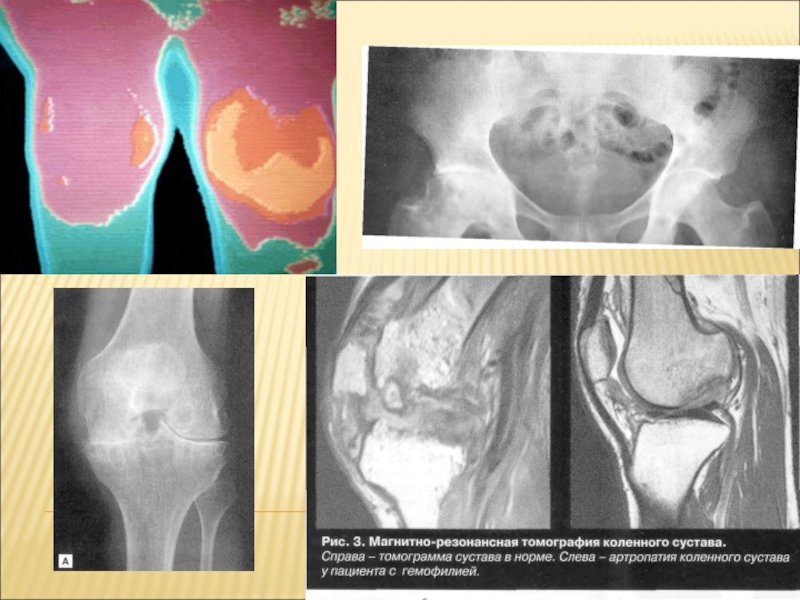

Слайд 11КРОВОИЗЛИЯНИЕ В КОЛЕННЫЙ СУСТАВ У БОЛЬНОГО ГЕМОФИЛИЕЙ.

КРОВОИЗЛИЯНИЕ В КОЛЕННЫЙ СУСТАВ У БОЛЬНОГО ГЕМОФИЛИЕЙ.

Слайд 12Гемартроз коленного сустава у больного гемофилией

Гемартроз коленного сустава у больного гемофилией